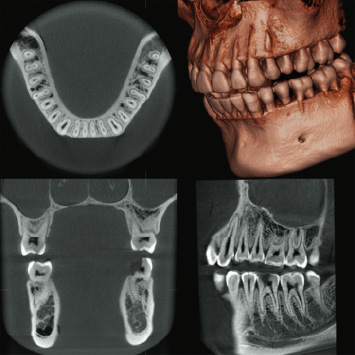

歯科用CT完備

CT(コンピュータ断層撮影)とは、コンピュータを駆使してデータ処理と画像を解析してそれぞれの断面の画像を撮影する技術です。

歯科用CTとは歯科分野に特化したCT装置のことであり、一般の医科用CTと比べ被曝量が1/10と少ないのが大きな特徴で、撮影時間も十数秒で済むことから患者様への負担を大幅に軽減することができます。

また、歯科用CTでは、歯が失われた部分の骨の厚みや深さ密度、上顎洞や下顎管までの距離を正確に計測し、三次元的に立体的に把握できるデータを得ることができます。

歯科用CTを活用することにより診断・治療の精度を大きく向上させることが可能となります。